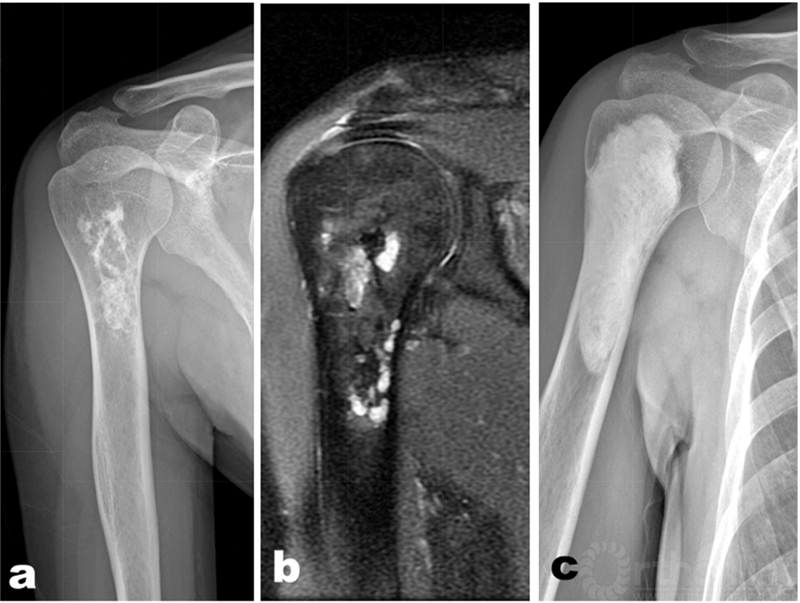

对于累及干骺端的低度恶性的软骨肉瘤,通过囊内刮除虽然最大限度的保留了关节功能,但是因为病变原因通常会使骨的抗应力能力降低,导致骨折风险加大,因此选用合适的功能重建,对恢复患肢的功能非常重要。使用骨水泥进行骨的重建是常用的方法之一。骨水泥硬化过程中发热可以通过温度疗法杀灭残存肿瘤细胞;可以通过病变处进行良好的塑形;不会产生自体骨移植所导致的供区缺损;同时也有助于从影像学上观察病变组织是否完全切除及是否有复发;也可以作为钢板螺钉固定的界面。另外一些方法包括自体或异体骨移植,钢板螺钉系统固定等方法。虽然髓内钉系统可以增加骨的稳定性,但是髓内钉可能将病变细胞带到毗邻部位的正常组织中,因此不推荐使用[3,16]。(图2[18])

图2:47岁中年女性,术前X片提示软骨结节样钙化(a),术前MRI提示骨皮质部分受累(b),使用囊内扩大刮除+骨水泥填充,术后5年X片未提示复发(c)